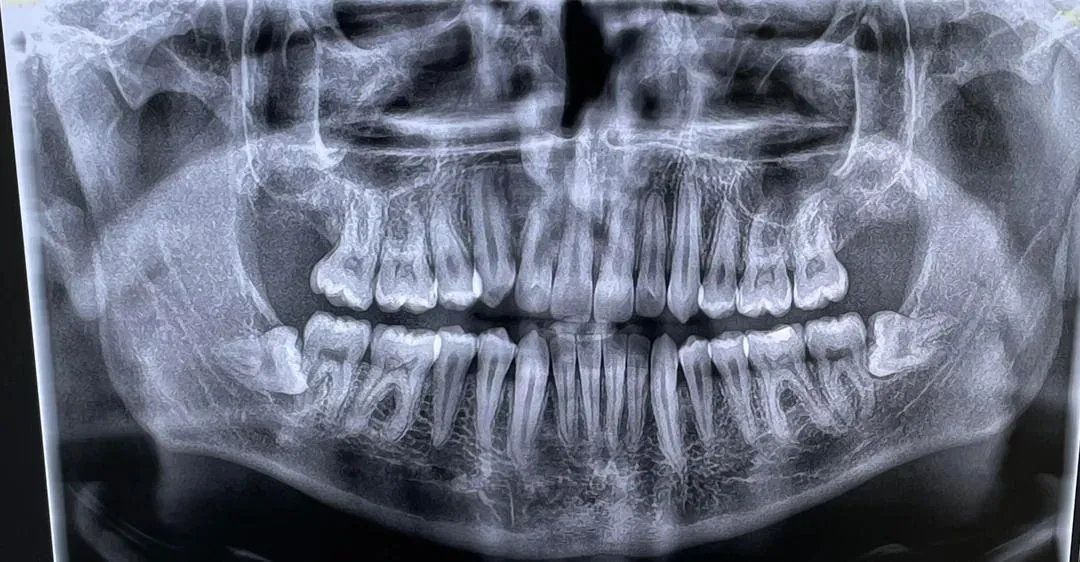

Comprehensive Evaluation & Digital X-Rays

Your treatment begins with a thorough examination at Lifetime Smiles Dental Care, where we take detailed digital X-rays to assess the position, growth, and potential impact of your wisdom teeth. This allows us to determine whether extraction is necessary and helps us plan the best approach for your individual case.